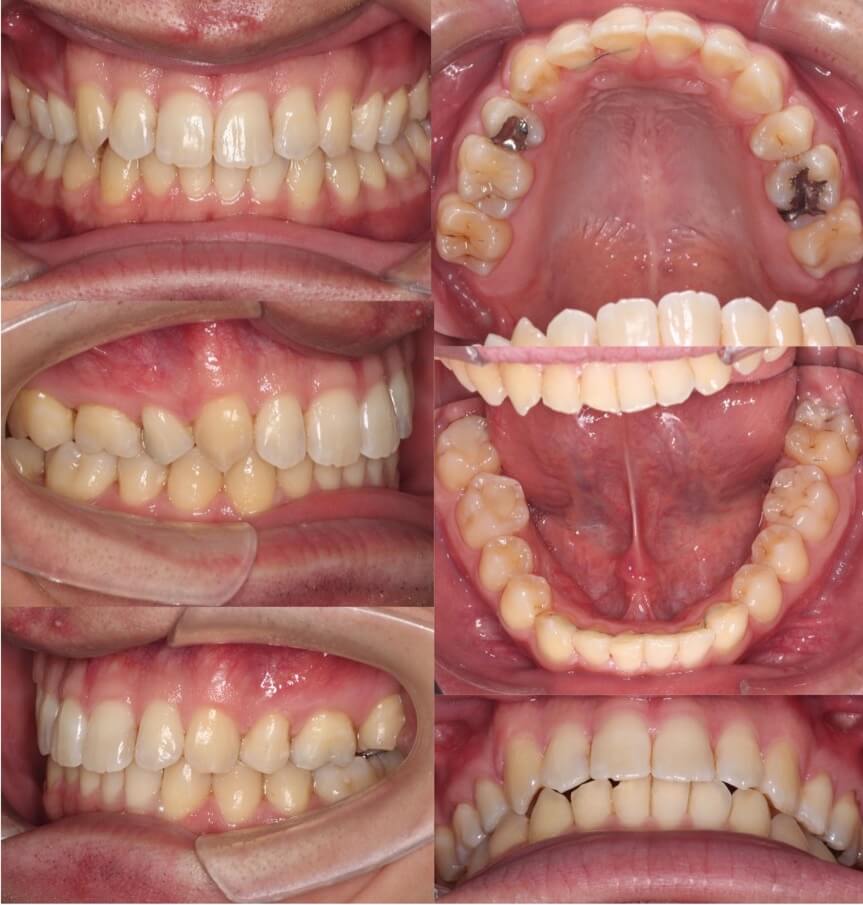

20代男性・マウスピース型矯正装置・上抜歯

マウスピース型矯正治療に向いている典型的な上のみの抜歯症例です。このようなケースは治療期間も短く終了できます。

<症例概要> 難易度★★★☆☆

主訴:上の前歯の前突

年齢・性別:20代男性

住まい:千葉県習志野市

症状:上顎前歯唇側傾斜・叢生・右6番交叉咬合・正中線不一致

治療方針:上顎抜歯空隙閉鎖・下顎歯列拡大・IPR

治療装置:マウスピース型矯正装置(アライナー装置)

抜歯:上左右4番(計2本)

治療期間:1年7か月

アライナー枚数:60+20ステージ(1週間交換)

リテーナー:上下フィックスタイプ+クリアタイプ

治療費用:990,000(税込)

代表的副作用:痛み・治療後の後戻り・歯根吸収・歯髄壊死・歯肉退縮

▶︎その他の副作用

【治療シミュレーション】

上はゆっくりと抜歯空隙を閉鎖しています。

臼歯の交叉咬合を治すために、下の歯を順番に後方移動させています。